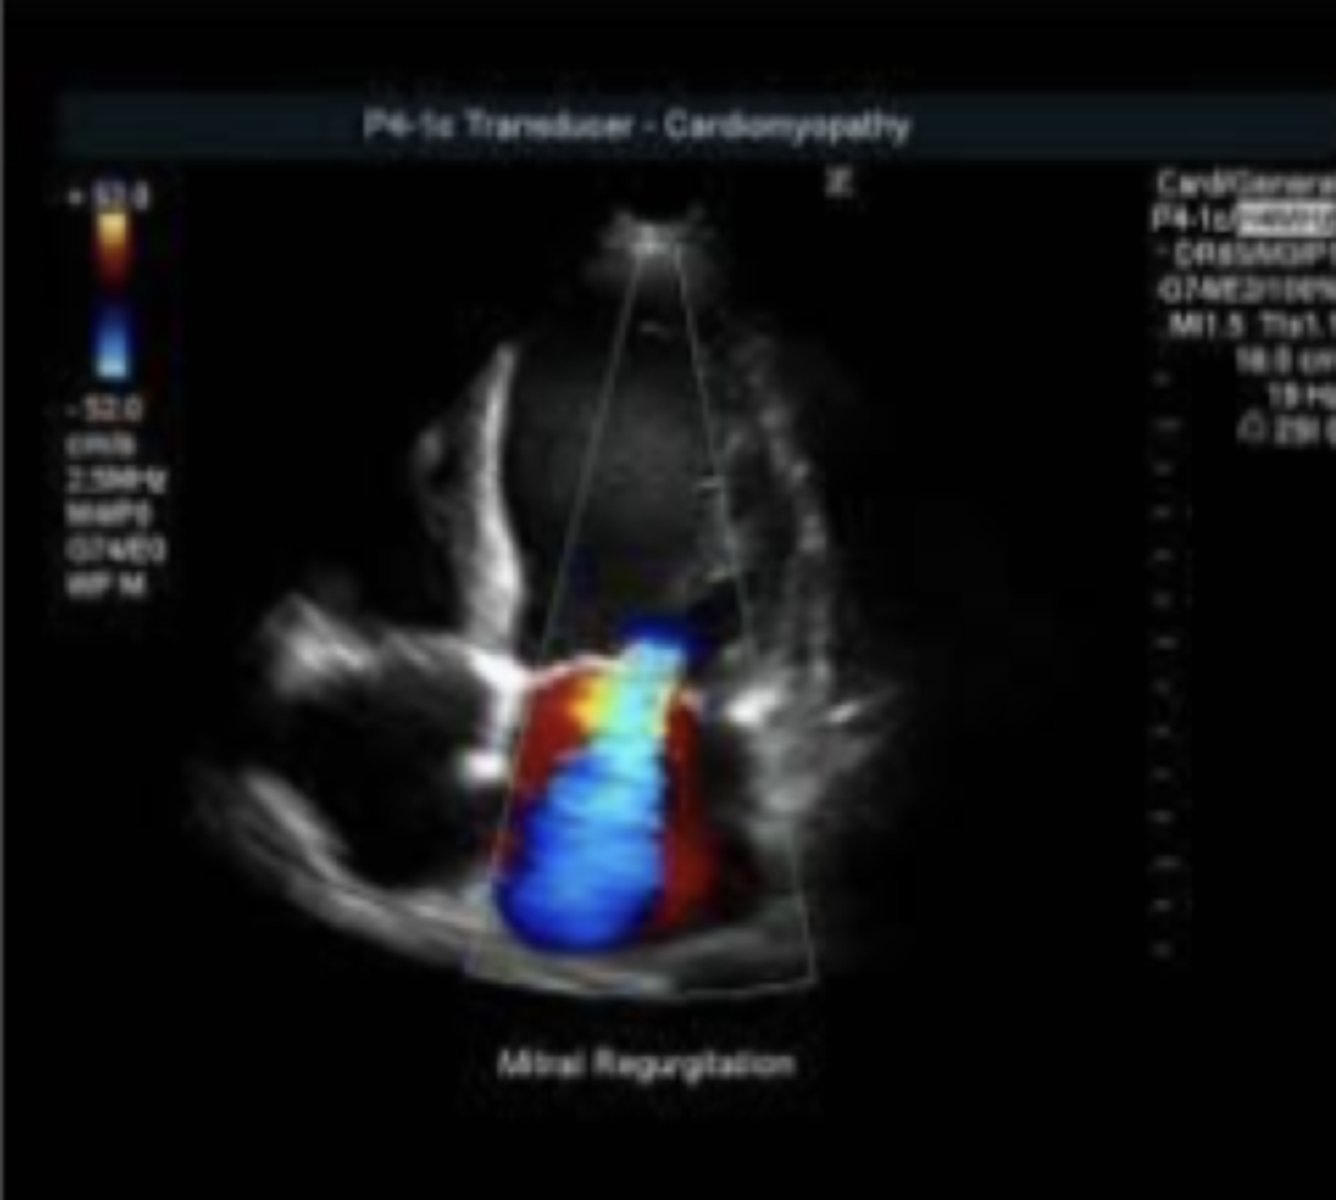

cardiomiopatía dilatada

(perros)

patología:

eco

RMN

¿cuál técnica de imagen utilizaría para diagnosticar una valvulopatía?

¿cuál técnica de imagen utilizaría para diagnosticar una miocardiopatía?

pulso espectral: registrar la velocidad, dirección, y tipo de flujo sanguíneo

pulso color: información sobre tamaño, forma, y estructura del corazón

¿para qué utilizamos ecocardiografía Doppler?